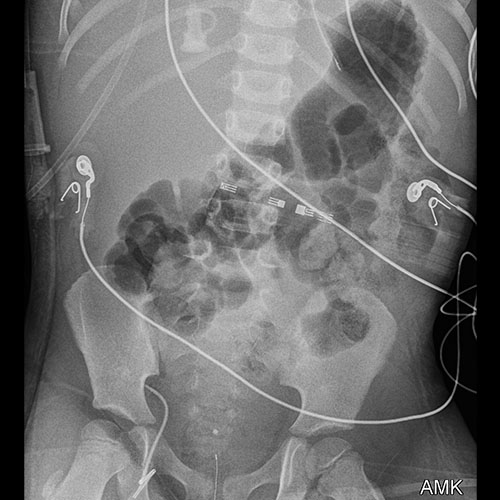

There are additional lines, tubes, catheters, or drains in place. (e.g. chest tubes, mediastinal drains, rectal temp probe, etc.)

​Both the small and large bowel are filled with air and/or fluid and may or may not be distended.